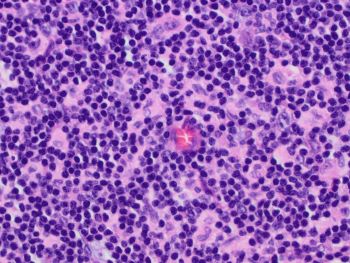

Images 1 and 2 show an enlarged lymph node with mostly intact architecture and marked paracortical expansion with pale staining areas. The expansion is mostly nodular. Although, areas of diffuse paracortical expansion are seen, such as on the left side of image 2. Images 3 and 4 show pale staining areas at high power magnification from different parts of the lymph node. Image 3 shows Langerhans and interdigitating dendritic cells with mostly small lymphocytes in the background. Image 4 shows Reed Sternberg cells with a mixed background of histiocytes, small lymphocytes, eosinophils, and plasma cells.

CD30 is positive in the Reed Sternberg cells of CHL and negative in Langerhans/dendritic cells. CD15 is not as helpful since it is negative in about 1/4 of CHL. CD20 is usually negative in CHL and would not help distinguish. CD3 would be negative in both, and both would show a similar background rich in T-cells.

CHL is part of the differential diagnosis for dermatopathic lymphadenopathy (DL). The pale areas can resemble the Reed Sternberg cells and histiocytes of CHL and vice versa. An added challenge is when CHL shows an interfollicular growth pattern (seen in this case) without marked distortion of the lymph node architecture. provides an extra challenge in showing relatively preserved nodal architecture. High power examination of the pale areas for Reed Sternberg cells will distinguish the two with immunohistochemical studies performed if needed (CD15, CD30, PAX5, CD45, etc.).